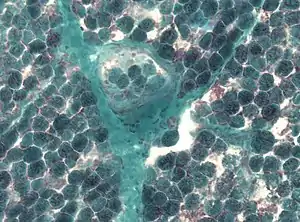

| |

| Detection of numerous ragged red fibers in a muscle biopsy | |